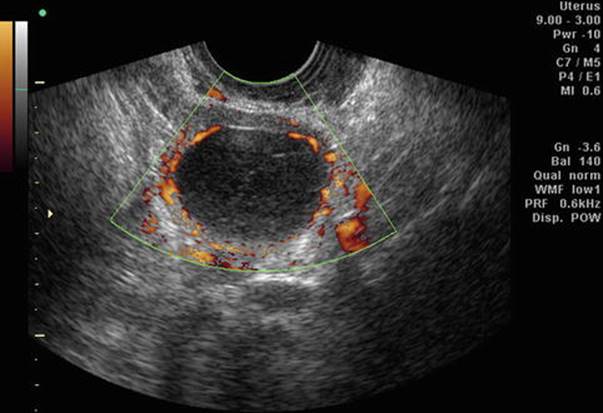

Fig. 2.7

Corpus luteum with increased peripheral blood flow

Doppler in the secretory phase gives an idea about the function of corpus luteum (CL). Usually, the RI of the corpus luteum (Fig. 2.15) is between 0.35 and 0.50. In luteal phase deficiency (LPD), RI is 0.58 ±0.04, PI is 0.70–0.80, and PSV is between 10 and 15.

Fig. 2.15

Doppler of corpus luteum